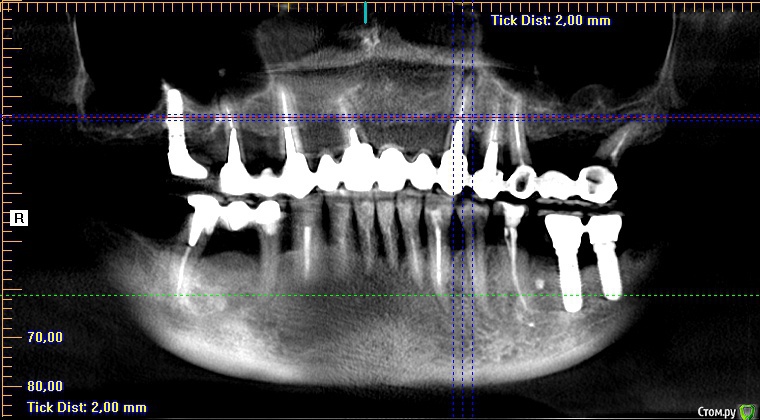

Тимур86 Опубликовано 12 февраля, 2019 Поделиться Опубликовано 12 февраля, 2019 планируется костная пластика 12-22. 23 впоследствии будет удалён,но киста перед нкр смушает...стоит рвк сделать,как думаете? Ссылка на комментарий

Nazim_NV86 Опубликовано 12 февраля, 2019 Поделиться Опубликовано 12 февраля, 2019 Во время НКР и сделайте. +5мин. Крайний правый пин перед очагом. Ссылка на комментарий